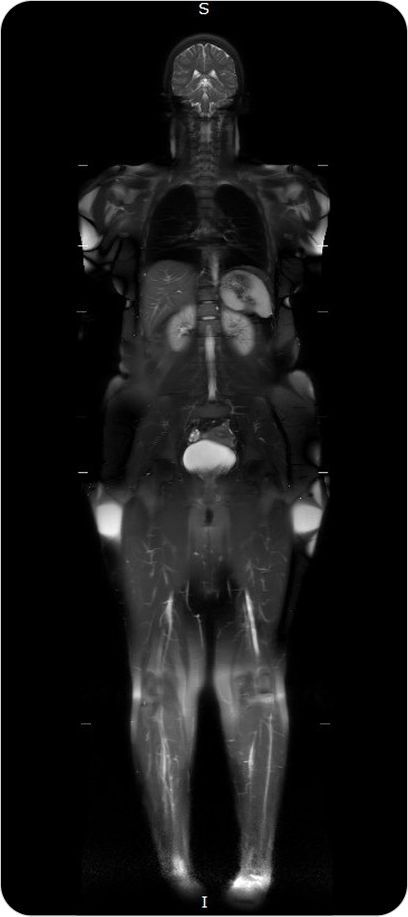

Resonancia Magnética Total

La resonancia de cuerpo entero permite examinar de forma integral todos los órganos y sistemas, sin utilizar radiación, siendo ideal para chequeos médicos preventivos y evaluación de enfermedades sistémicas.

Es un estudio no invasivo que permite visualizar de manera integral el cuerpo humano, sin radiación. Ofrece imágenes de alta resolución de órganos, tejidos blandos, sistema musculoesquelético y más.

¿PARA QUE SE UTILIZA?

- Detección precoz de tumores, lesiones o inflamaciones en órganos.

Seguimiento de pacientes oncológicos. - Evaluación del estado general de salud en chequeos preventivos.

Estudio de enfermedades musculares, articulares o neurológicas que afectan varias zonas del cuerpo. - Detección de metástasis o lesiones ocultas.

¿POR QUÉ ES UN ESTUDIO DESTACADO?

- Cobertura completa del cuerpo en una sola sesión.

- Sin uso de radiación.

- Alta sensibilidad para detectar lesiones incluso cuando son pequeñas.

- Muy útil en chequeos médicos de prevención de enfermedades graves.

Resonancia Magnética Total

La resonancia de cuerpo entero permite examinar de forma integral todos los órganos y sistemas, sin utilizar radiación, siendo ideal para chequeos médicos preventivos y evaluación de enfermedades sistémicas.

Es un estudio no invasivo que permite visualizar de manera integral el cuerpo humano, sin radiación. Ofrece imágenes de alta resolución de órganos, tejidos blandos, sistema musculoesquelético y más.

¿PARA QUE SE UTILIZA?

- Detección precoz de tumores, lesiones o inflamaciones en órganos.

Seguimiento de pacientes oncológicos. - Evaluación del estado general de salud en chequeos preventivos.

Estudio de enfermedades musculares, articulares o neurológicas que afectan varias zonas del cuerpo. - Detección de metástasis o lesiones ocultas.

¿POR QUÉ ES UN ESTUDIO DESTACADO?

- Cobertura completa del cuerpo en una sola sesión.

- Sin uso de radiación.

- Alta sensibilidad para detectar lesiones incluso cuando son pequeñas.

- Muy útil en chequeos médicos de prevención de enfermedades graves.